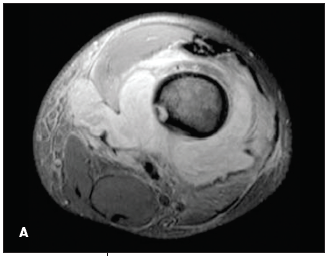

Severino R. Bautista, MD; Purushottam Gholve, MD; John P. Dormans, MD

Musculoskeletal infections in children include osteomyelitis, septic arthritis, and pyomyositis. Most of these infections are bacterial.

Musculoskeletal infections in children include osteomyelitis, septic arthritis, and pyomyositis.